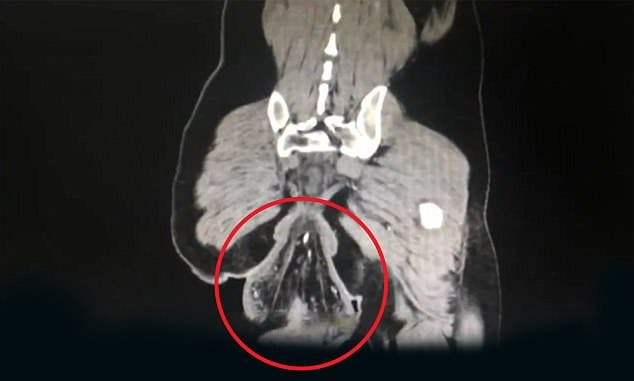

Una tomografía computarizada (TC) mostró un bulto en forma de bola fuera del ano del paciente, el bulto tenía un diámetro de 16 centímetros, el Dr. Su dijo que había hematomas y manchas de sangre a lo largo de la pared intestinal del paciente.